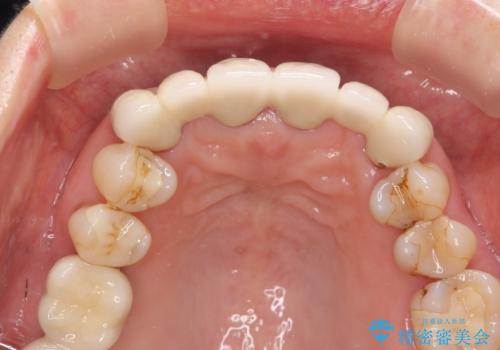

不自然な前歯ブリッジ ジルコニアブリッジによるやり替え

- 20年前に入れたブリッジの見た目の改善を求めて来院されました。

丁寧に現在装着されているブリッジを除去後、精度の高いジルコニアブリッジで審美性の改善を計画します。

- 66万円(仮歯・ジルコニアクラウン×6)費用は治療当時の料金となります

前歯に限らず拡大鏡を用いた精密な形成・シリコンを用いた精度の高い印象を徹底することで治療全体の質を高め、審美性だけでなく長期的な予後を期待することができます。